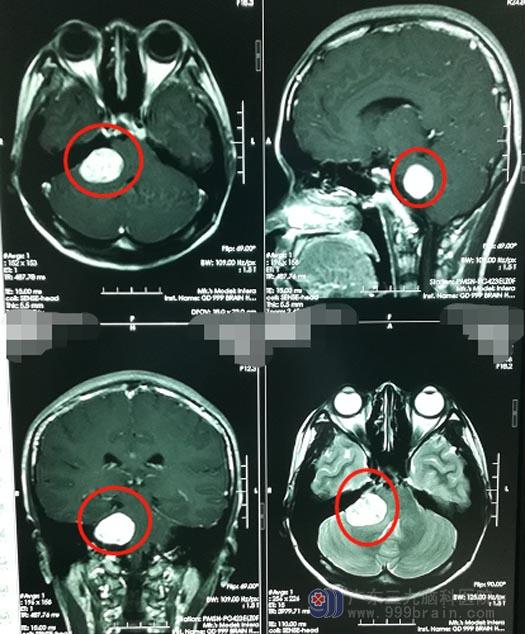

24岁的小珍,半年前开始出现右侧面部麻木,由于没有其它不适症状,所以也就没有引起重视。近2个月来,小珍出现右侧耳鸣,伴听力下降,并且越来越严重。在当地医院就诊,头颅MR检查提示“右侧桥小脑角占位性病变,考虑听神经鞘瘤”,医生建议手术治疗。

父母打消了顾虑,小珍也增强了战胜疾病的信心。充分的术前准备后,鲁明带领团队为小珍实施了“右侧桥小脑角区神经鞘瘤切除术”,在显微镜下分块切除肿瘤及大部瘤膜,肿瘤大小约3cm×3cm×3cm,上至三叉神经,下达末组颅神经,与面听神经及脑干明显粘连,内听道内的肿瘤也被完整切除,同时兼顾了对周边神经、血管解剖的保护,面听神经解剖保留。手术完成顺利。